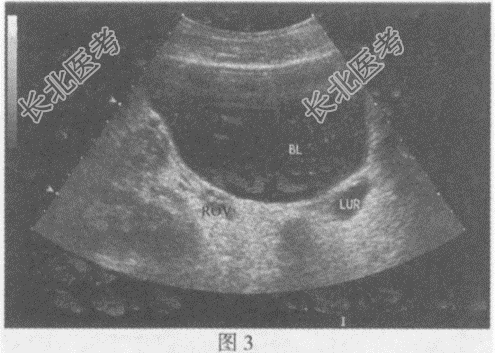

- 单项选择题临床资料:女, 9岁,自述左侧腰部疼痛2年余。

超声综合描述: 左肾增大,上极部集合系统内可见4.3cm×3.1cm无回声(图1), 形态不规则;下极部集合系统未见分离。左输尿管全程显示(图2、图3), 内径1.7~2.7cm,左输尿管末端可见一类圆形无回声区突向膀胱内(图4), 囊壁薄而清晰、规则,动态观察无回声区大小随左输尿管蠕动有节律变化。